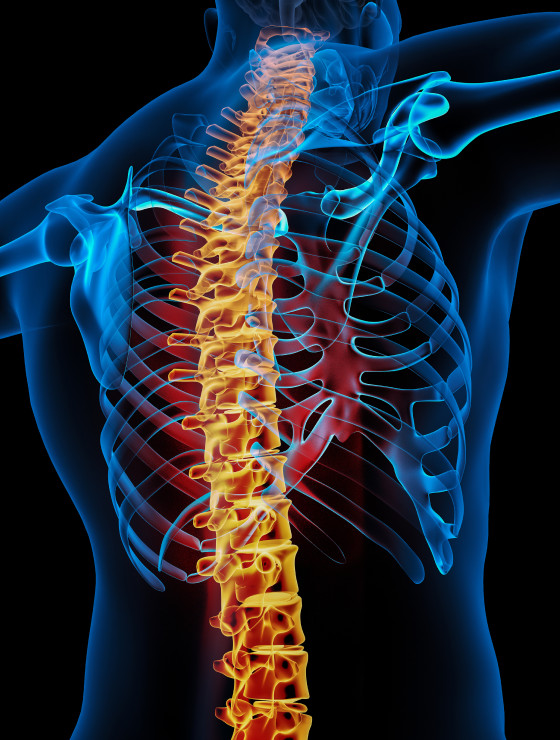

Cirurgião especializado no diagnóstico, tratamento e correção de problemas da coluna vertebral.

Dr. Fernando Soccol é médico ortopedista referência em cirurgia da coluna vertebral, com mais de uma década de experiência, expoente na área de cirurgia minimamente invasiva e cirurgia endoscópica da coluna.

Cirurgias na coluna são seguras e previsíveis. Ao longo das últimas décadas observou-se refinamento das técnicas operatórias e dos equipamentos de projeção de imagens, como microscópios e vídeo-endoscópios. Hoje é possível “navegar” em cirurgias guiadas por tomografia tridimensional, além de monitorar a atividade neurológica do paciente em tempo real.